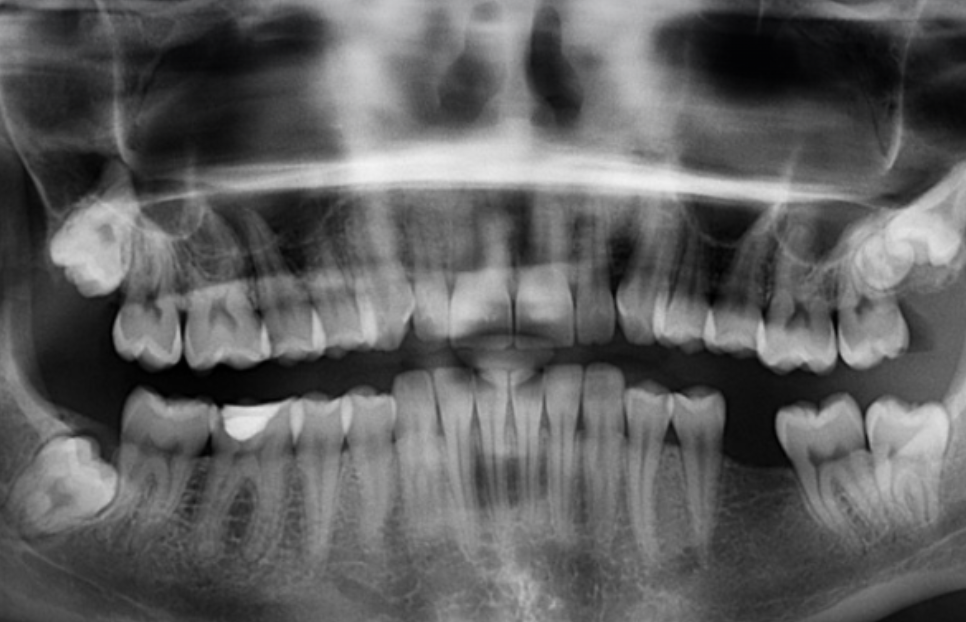

사랑니는 정상적으로 자라는 경우 무조건 발치할 필요는 없으나, 비정상적으로 자라 잇몸 아래에 충격을 가하면 칫솔이 닿기 어려워 충치가 쉽게 생겨날 수 있습니다. 잇몸의 일부가 밀려나 감염이 생기기 쉽기 때문이지만, 무조건적인 발치를 권하지 않습니다. 하지만 나이가 들수록 문제가 생기는 경우가 많이 있기는 합니다.